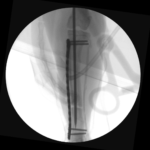

最小侵襲整形外科 脛骨を骨折した猫が足を痛がっているので手術して欲しいと主治医から連絡がありました。外科用イメージを使って、髄内ピンとプレートによる固定術を行い、翌日退院しました。この手法は皮膚や筋肉を大きく切開しないというメリットがあります。 症例カテゴリー 放射線治療整形外科軟部組織外科脳神経外科内科腫瘍外科救急・集中治療リハビリテーション科腫瘍内科内視鏡科脳神経科呼吸器外科中医・漢方猫の腎移植循環器科